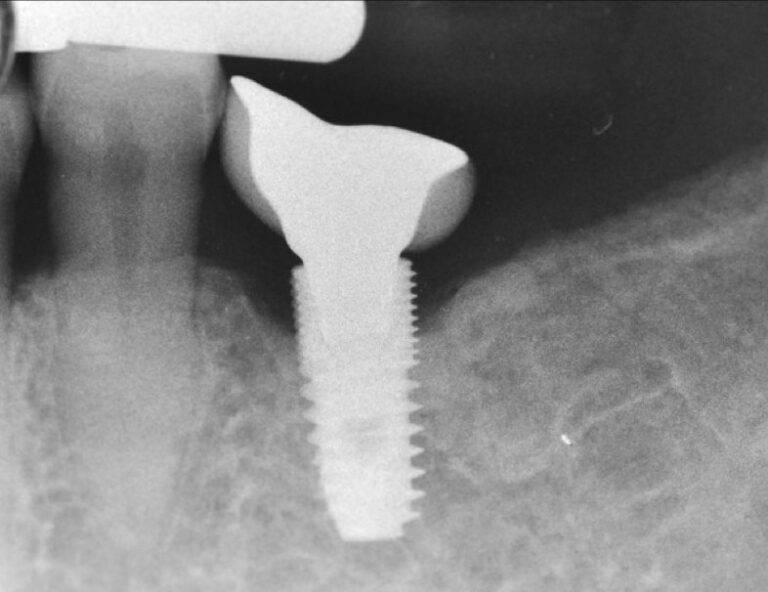

A similar problematic prosthesis design as before, only here directly on the bone level platform. No surprise that we run out of luck with this design and we can’t blame the bone level implant for the marginal bone loss…